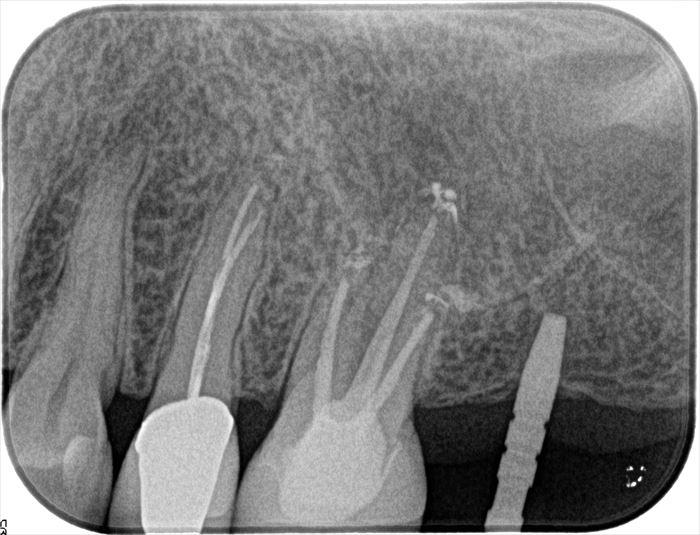

デンタルレントゲン写真です。

予定通りの角度にドリリング出来ていますので、深さ及び太さを拡大していきます。